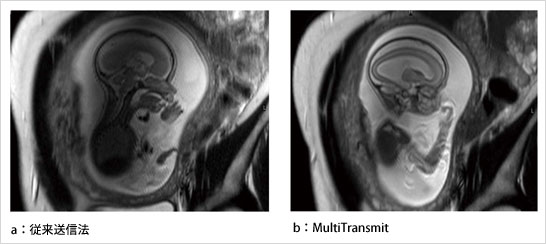

図2は,MultiTransmitで撮像された15名の乳腺のボランティア画像(左:3D T1W,右:脂肪抑制併用3D T1W)の3列表示である。大きさや形状が異なる場合でも,均一な信号強度や脂肪抑制効果が確保されていることがわかる。図3には,腹水および脾臓に拡張を認める患者を従来送信法で撮像した画像(図3 a,c)およびMultiTransmitで撮像した画像(図3 b,d),図4では胎児を従来送信法で撮像した画像(図4 a)とMultiTransmitで撮像した画像(図4 b)を比較している。MultiTransmitにより,従来,信号不均一の影響で困難であった検査も可能となることがわかる。

図4 胎児を撮像したケース

(Courtesy : University of Vermont, USA)